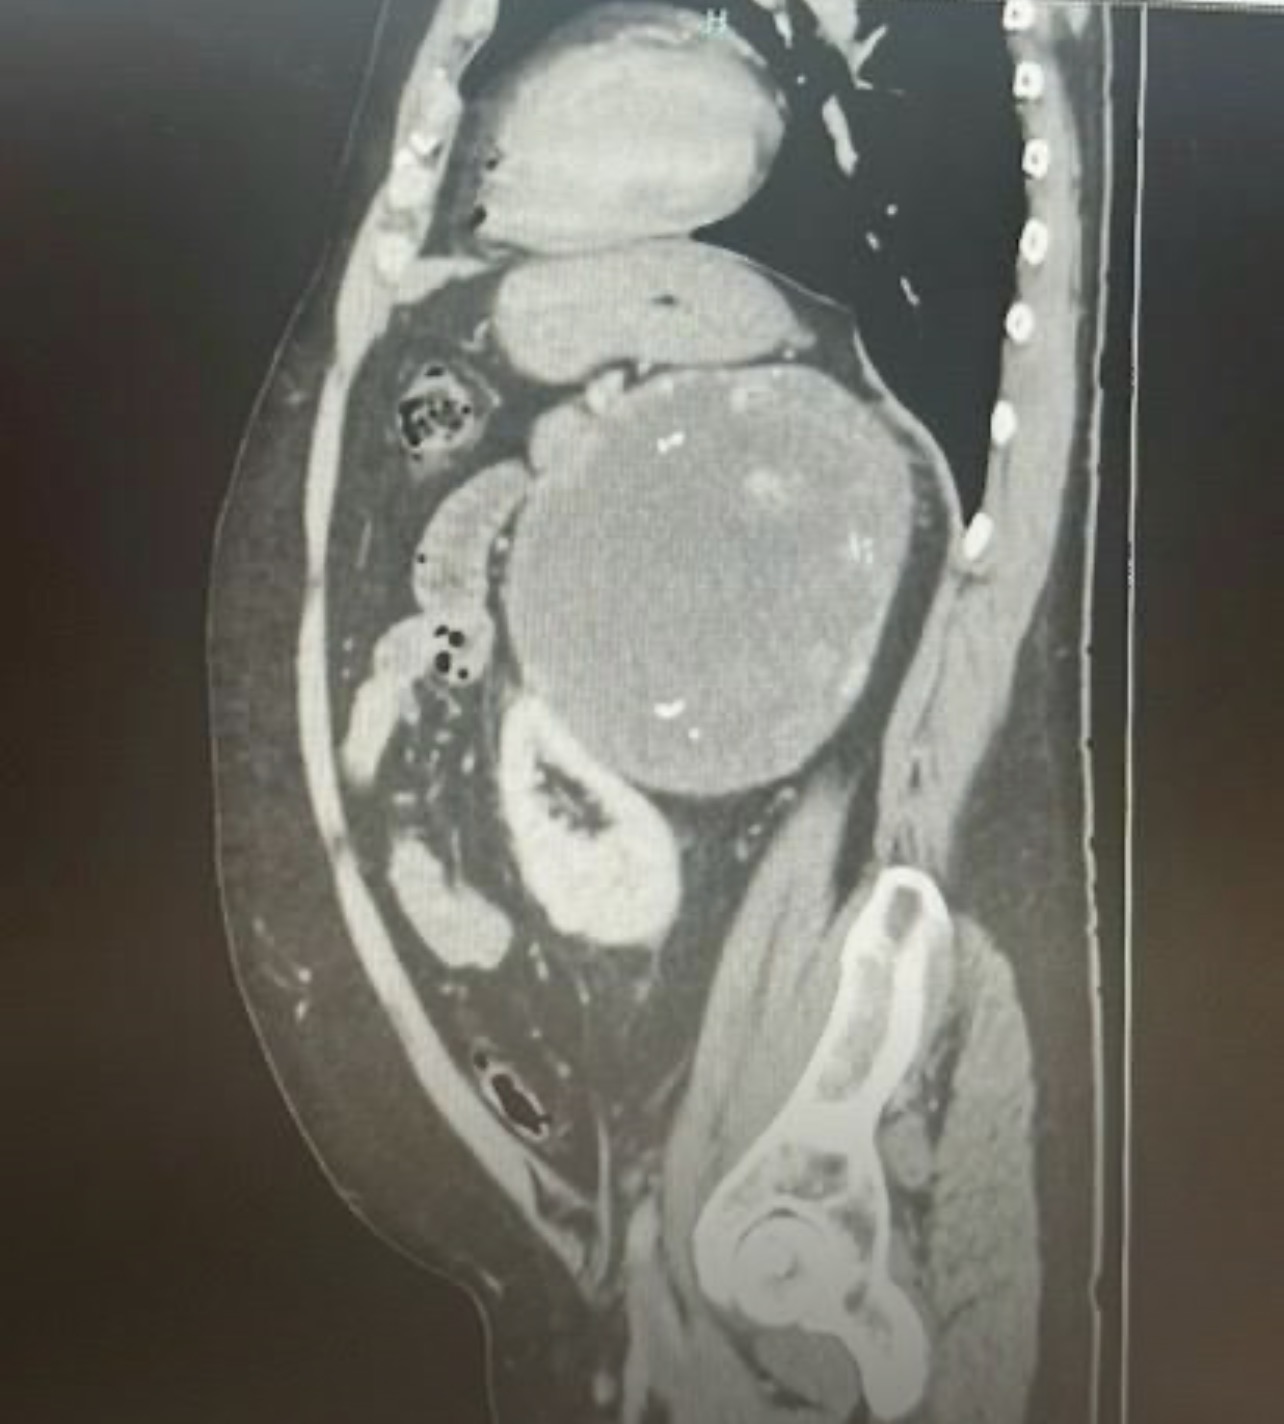

Imagen Urologo las palmas

Imagen urologo bloque informacion